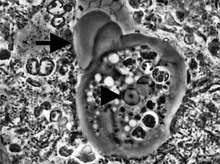

It is found in the mouth[5] inside the gingival pocket biofilm near the base of the teeth, and in periodontal pockets.[1] Entamoeba gingivalis is found in 95% of people with gum disease and rarely in people with healthy gums.[6][7] Cyst formation is not present; therefore transmission is direct from one person to another by kissing, or by sharing eating utensils. Only the trophozoites are formed and the size is usually 20 micrometers to 150 micrometers in diameter. Entamoeba gingivalis have pseudopodia that allow them to move quickly and phagocytise the nucleus of polynuclear neutrophils by exonucleophagy in periodontal disease.[8] Their spheroid nucleus is 2 micrometers to 4 micrometers in diameter and contains a small central endosome. There are numerous food vacuoles, which consists mostly of phagocitised PMN nucleus, blood cells and bacteria.

The main activity of the amoeba Entamoeba gingivalis in the infected periodontal crevices, besides moving, consists in feeding on the nucleus of white blood cells. The amoeba penetrates into the cytoplasm to reach the nucleus and literally suctions its contents via the negative pressure of the pseudopod. The food so gulped down is gradually digested inside the endoplasm. Phagocytosis can sometimes continue for more than 20 polynuclear neutrophil nuclei. This activity leaves a denucleated cell, unable to achieve either its NETS activity or its preprogrammed apoptosis. It will release PMN-uncontrolled proteolytic enzymes on surrounding tissues and could be considered a pathogen from this vampirising activity.